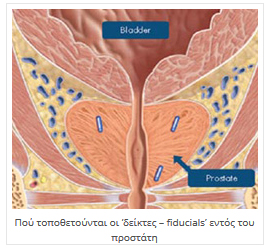

Προϋπόθεση είναι η τοποθέτηση εντός του προστάτη αδένος, τριών έως τεσσάρων "δεικτών αναφοράς" (3 – 4 fiducials), οι οποίοι εντοπίζονται από το σύστημα κεντροθετήσεως, και ανάλογα με τις μικρομετακινήσεις του στόχου, δίδεται εντολή και ο ρομποτικός βραχίονας διορθώνει την απόκλιση της δέσμης από εκατοστά έως δέκατα του χιλιοστού.

Η τοποθέτηση των "δεικτών αναφοράς" (κομμάτια σύρματος καθαρού χρυσού μήκους πέντε και πάχους 0,8 χιλιοστών (5 Χ 0,8 mm) εμφυτεύονται στον προστάτη με λεπτή βελόνα (18 G) υπό ενδορθική υπερηχογραφική καθοδήγηση.

Οι «δείκτες – fiducials» είναι μικρά κυλινδρικά κομμάτια καθαρού χρυσού (Au 99,9 %) χωρίς ίχνος ακτινοβολίας, μήκους 5 χιλιοστών που εμφυτεύονται μέσα στον προστάτη αδένα όπου θα γίνει και η θεραπεία με CyberKnife®.

Με τον τρόπο αυτό, το ψηφιακό σύστημα αναγνωρίζει τη σωστή θέση του στόχου ανά πάσα στιγμή και σε περίπτωση κινήσεώς του, ο ρομποτικός βραχίονας να κάνει τις ανάλογες διορθώσεις ώστε να υπάρχει πάντα απόλυτη ευστοχία των δεσμών ακτινοβολίας που θα στείλει το σύστημα.

Πώς τοποθετούνται;

Οι «δείκτες – fiducials» είναι τοποθετημένοι μέσα σε λεπτές ειδικές βελόνες (δεν διαφέρουν σε διάμετρο με αυτές των αιμοληψιών) και εμφυτεύονται στο προστάτη υπό καθοδήγηση διορθικού υπερηχογράφου από ειδικό Ουρολόγο ή Ακτινοθεραπευτή Ογκολόγο. Πριν εμφυτευτούν, γίνεται κάποια προετοιμασία του εντέρου, ίδια ή παρόμοια με αυτή που έγινε προ της βιοψίας.

Για να γίνει η θεραπεία, πρέπει να υπάρχει σχετική ακινησία της περιοχής και εντοπισμός του στόχου. Για την ακινησία, γίνεται κατασκευή εξατομικευμένου αφρώδους στρώματος για μείωση των κινήσεων της πυέλου και των κάτω άκρων με διαδικασία αναίμακτη και μη επεμβατική. Για τον εντοπισμό του στόχου, χρειάζεται η τοποθέτηση "δεικτών" (fiducials – markers) μεγέθους 5 χιλ. μέσα στο προστάτη αδένα για να υπάρχει στόχευση με απόλυτη ακρίβεια. Η τοποθέτηση γίνεται με διορθικό υπερηχογράφημα και τοπική αναισθησία.